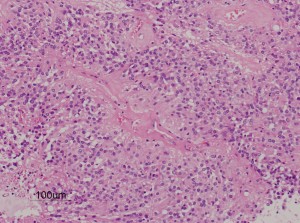

第4脳室床に発生した典型的な上衣腫 EPN-PFA の画像です。水頭症になって,頭痛と嘔吐,意識障害で発症しました。典型的なMRI画像と病理所見です。MRIでは第4脳室からマジャンディー孔を越えて脊髄背側まで長く腫瘍が伸びています。腫瘍内部に小さなのう胞が複数みられます。病理像では,血管周囲に細胞核がない無核野が認められます。血管周囲に伸びた繊細な単極性突起が集まった領域です。これは,血管周囲偽ロゼット perivascular pseudorosette という上衣腫に特徴的な病理所見です。

摘出した標本のHE染色です。左側ではperivascular pseudorosette(血管周囲の無核野)がみられ,右側ではependymal tube (ependymal canal) が認められます。

グレード2の組織像です。血管周囲に無核野があり,腫瘍の核は血管から離れているパターンが特長です。perivascular pseudo-rosetteといいます。